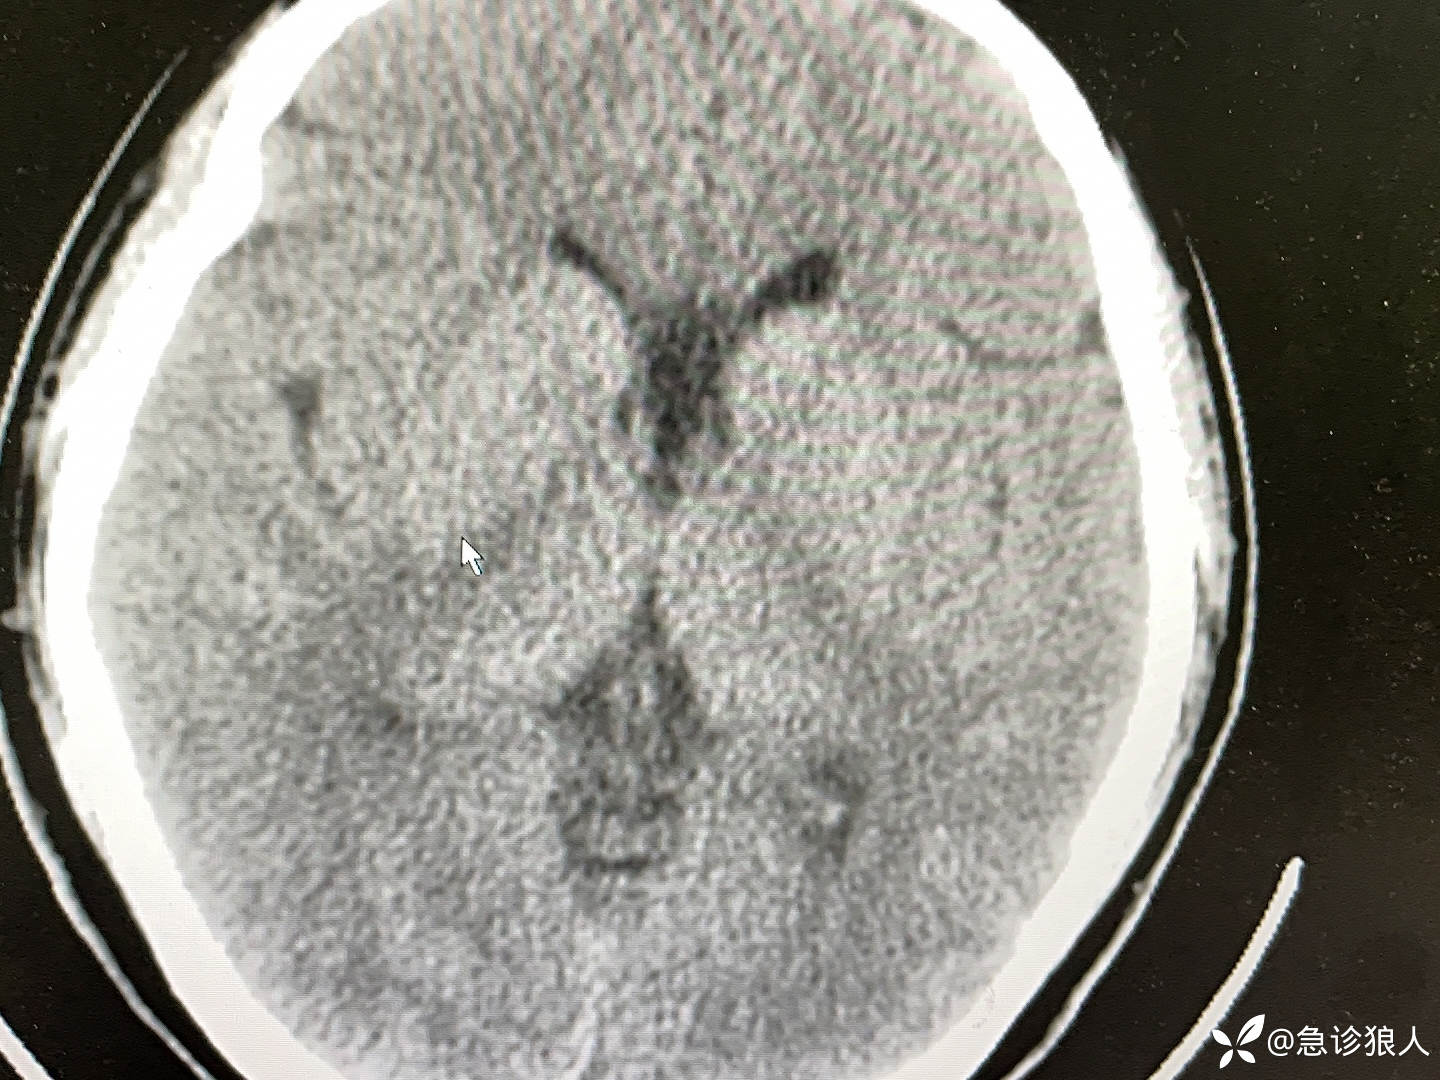

我问,“这是咋了呀?”

“高热,间断头部扭到一侧8.5小时,5天口服喹硫平过量,去急诊监护室做了灌流,就回家了。”

“嗯,我知道家属让回家上学,不配合治疗,但喹硫平不会导致这样。”

神经内科医生问,“恶性综合症?”

“不是啊,很明显的锥体外系反应,神志是清的,对了他长期吃丙戊酸镁,这几天可能没吃,这个药可以导致。”

这个小姑娘的血检结果具体如下:

诊断很明确吧!

很快就被收入重症监护室了!